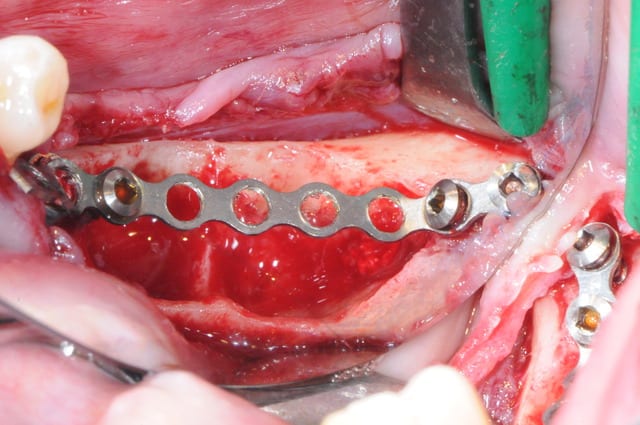

4-5-6-7 sciage de la mesh titane et positionnement in situ d'un bout à l'autre de l'arcade.

1-2

enfin, mise en place d'une membrane péricarde Jason de 30*50 (je crois)

3- j'ai profité de la stabilité de la mesh comme piquet de tente pour bourrer la cavité avec du MAXGRAFT (os humain)..